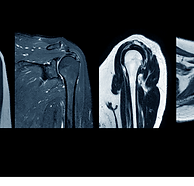

Your shoulder is made up of three bones: your upper arm bone (humerus), your shoulder blade (scapula), and your collarbone (clavicle). The shoulder is a ball-and-socket joint: the ball, or head, of your upper arm bone, fits into a shallow socket in your shoulder blade. Your arm is kept in your shoulder socket by your rotator cuff. The rotator cuff is a group of four muscles (supraspinatus, infraspinatus, teres minor and subscapularis)that come together as tendons to form a covering around the head of the humerus. The rotator cuff attaches the humerus to the shoulder blade and helps to lift and rotate your arm. A lubricating sac is called a bursa between the rotator cuff and the bone on top of your shoulder (acromion). The bursa allows the rotator cuff tendons to glide freely when you move your arm. When the rotator cuff tendons are injured or damaged, this bursa can also become inflamed and painful.

When one or more of the rotator cuff tendons is torn, the tendon no longer fully attaches to the humerus's head. Most tears occur in the supraspinatus tendon, but other parts of the rotator cuff may also be involved. In many cases, torn tendons begin by fraying. As the damage progresses, the tendon can completely tear, sometimes with lifting a heavy object.